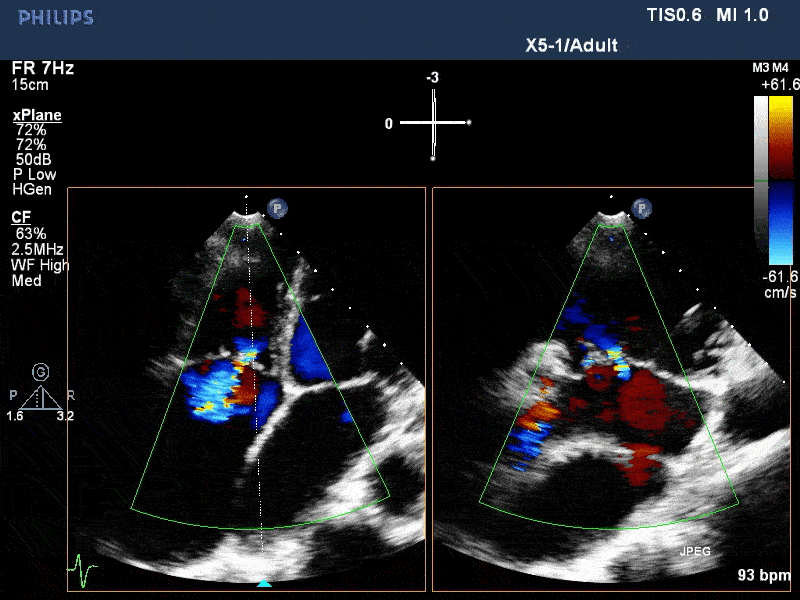

术前与术后即刻三尖瓣反流比较